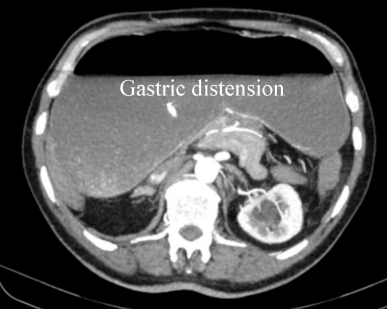

An emergency CT scan of the abdomen revealed a dislocation of the anatomical cardia to the right lower epigastrium and the gastric antrum to the left upper side (Figure 1 [Fig. 1]), spleen and tail of the pancreas were shifted medially (Figure 2 [Fig. 2]). The stomach appeared massively distended (Figure 3 [Fig. 3]). There was no free gas in the abdominal cavity and there were no direct signs of gastric gangrene.

Figure 3: CT scan: massively distended stomach